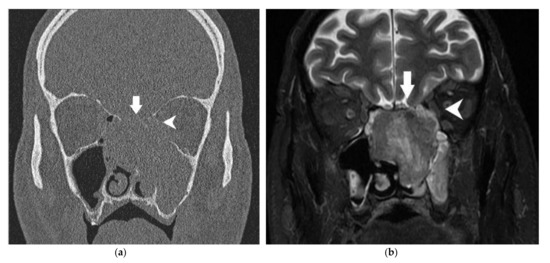

| Orbital bony walls | CT scanner | Contact without bony modification Minor (<2 mm) erosion Major (≥2 mm) erosion | Free Invaded |

| MRI | Minor (<2 mm) modification Major (≥2 mm) modification | ||

| Orbital bony walls | CT scanner | Contact without bony modification | 47 | 0% (0–7.6) | 0.85 | |

| Minor erosion | 22 | 27.3% (10.7–50.2) | ||||

| Major erosion | 43 | 48.8% (33.9–63.8) | ||||

| MRI | Minor modification | 21 | 28.6% (11.3–52.2) | 0.90 | ||

| Major modification | 40 | 47.5% (32.0–63.0) | ||||

| Orbital content | MRI | Invasion of the fat between tumor and oculomotor muscle | 24 | 33.3%(15.6–55.3) | 0.91 | |

| Deformation | Smooth | 45 | 28.6% (13.6–43.5) | 0.75 | ||

| Irregular | 6 | 33.3% (4.3–77.7) | ||||

| Contact angle | ≤45° | 40 | 21.2% (7.3–35.2) | 0.80 | ||

| >45° | 11 | 45.5% (16.8–76.6) | ||||

| Invasion of oculomotor muscle | 3 | 33.3% (0.8–90.6) | 1 | |||